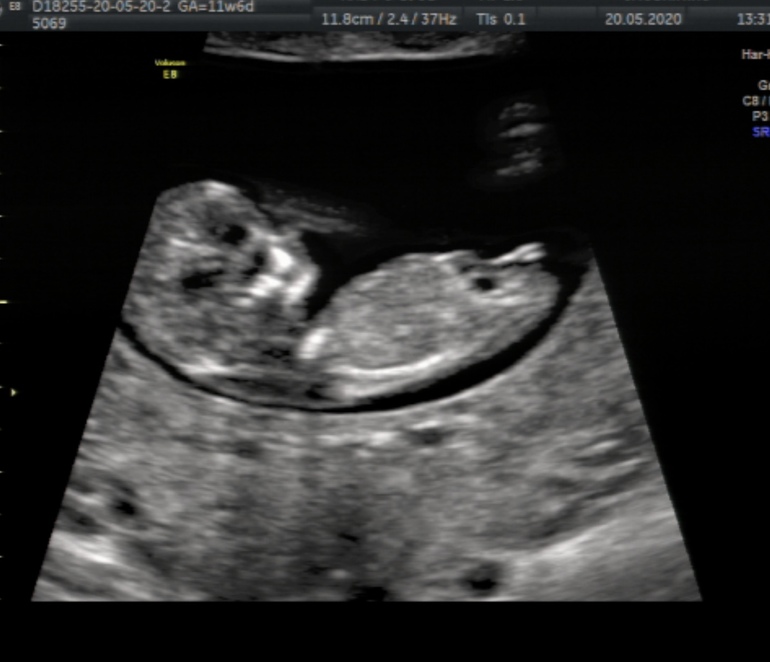

Любимый вопрос , как вы думаете кто в домике живет ?!😊

У меня с первым ребенком очень хорошая узистка в 12 недель сразу сказала мальчик, 200 %. Во второй раз сказала девочка, но на 90%. Типа, мальчиков сразу видно. Я тоже в ожиданиях/сомнениях находилась. Ну у вас как бы половой бугорок уж очень четко виден, девочкин.

Сказали что скорее всего , девочка )))) 100% на этом сроке не говорят )) так что Урааа❤️

У меня была точно такая картинка на мониторе, я прям на этот хвостик только и смотрела 😀Но мой врач предположила мальчика